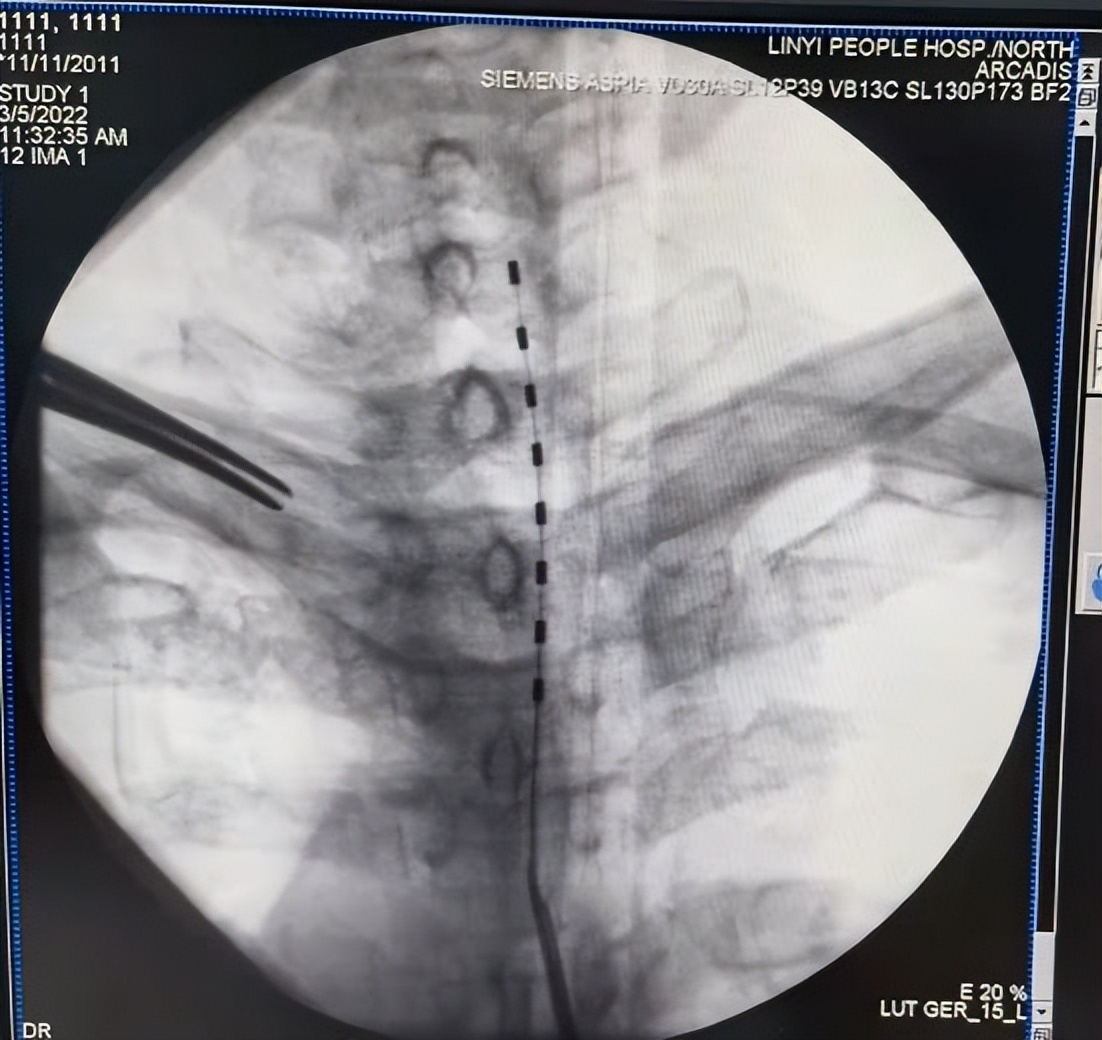

C型臂引导下将电极线置入右侧硬膜外腔

脊髓电刺激(Spinal Cord Stimulation,SCS)是一种安全、有效治疗多种慢性顽固性疼痛的方法,其通过植入脊髓硬膜外腔的电极导线将神经刺激器产生的电流传至脊髓,针对脊神经进行低压电电刺激,阻断疼痛信号上传到大脑中枢,达到缓解疼痛的效果;同时通过电流的刺激,也可以促进神经自身的修复。此手术具有创伤小、副反应轻、疗效持久及可调控的特点。脊髓电刺激的适应症主要有:带状疱疹后遗症、下肢缺血性疾病(糖尿病足、动脉硬化闭塞症等)、腰椎术后综合征(FBSS)、顽固性腰腿痛或下背痛(CBLP)、复杂性区域疼痛综合征(CRPS)、残/幻肢痛、脊髓损伤后疼痛等。

术中测试